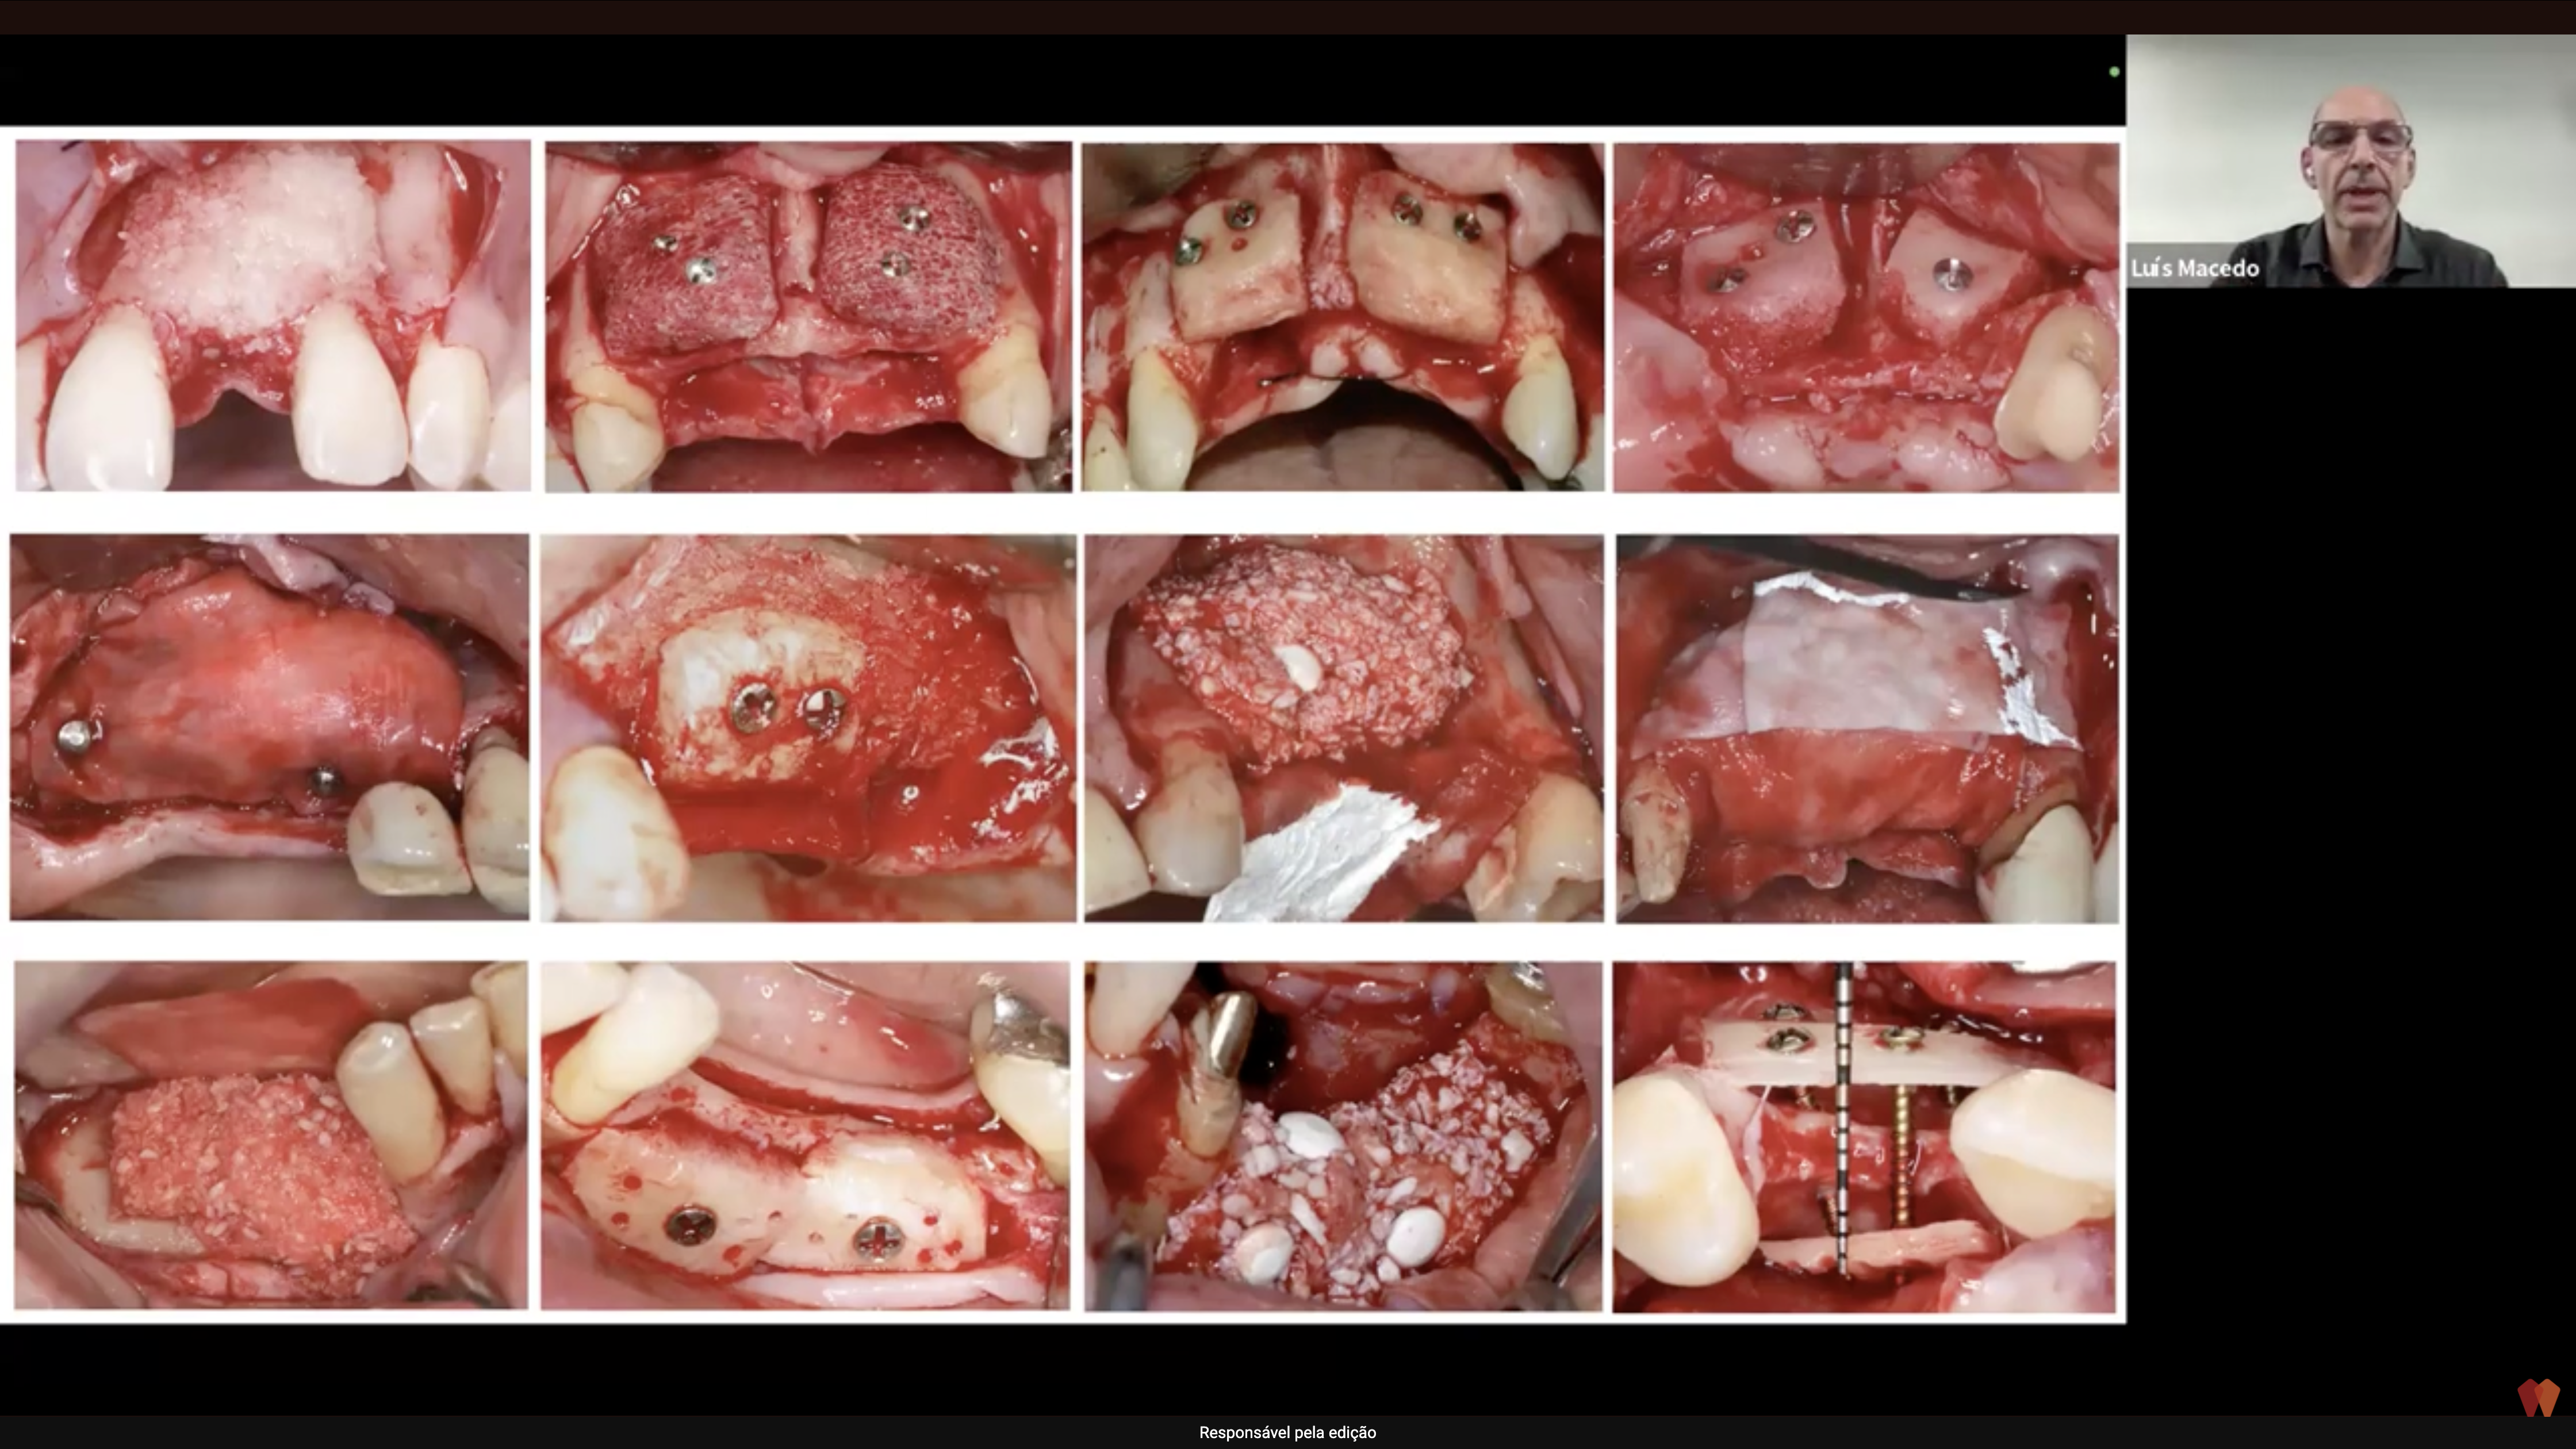

Técnica Laminar: o avanço que redefine a regeneração óssea guiada em defeitos complexos Como o equil...

Preservação de Rebordo e Implantes Imediatos na Área Estética: Como os Designs Biológicos Definem Re...

🦷 Preservação Alveolar para Implante Tardio: A Ciência, as Técnicas e as Decisões que Transformam R...

PRF Avançado na Odontologia: A Revolução Biológica Que Está Transformando Cirurgias e Regeneração Ós...